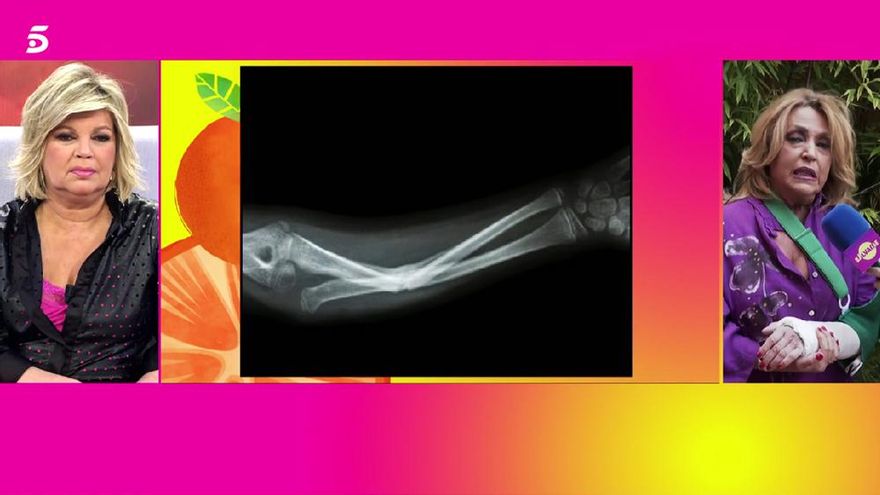

Sálvame está viviendo una de sus semanas más accidentadas. Si la semana comenzaba con la rotura de tibia y peroné de Belén Esteban en pleno directo, este viernes el magacín ha informado de la lesión de otra colaboradora habitual, Lydia Lozano. La periodista se ha roto el radio tras sufrir un percance doméstico.

La encargada de dar la información era Terelu Campos, al frente de la edición de este viernes. Tal y como ha explicado, la tertuliana se estaba calzando una bota estando de pie, ha perdido el equilibrio y ha caído al suelo. Para amortiguar el golpe, antepuso el brazo, provocándose la fractura diagnosticada luego en el hospital.

El programa no ha dudado en mostrar las radiografías de la lesión, dejando la entrevista para los detalles concretos de la convalecencia: por delante, 40 días con el vendaje, a la espera de salir alguna otra cuestión de rehabilitación. Su intención, ha dicho, es volver el lunes a ver a sus compañeros. Al menos, emplazaba a sus compañeros al comienzo de la siguiente semana para firmarle la escayola.

La radiografía de Lydia Lozano en 'Sálvame'